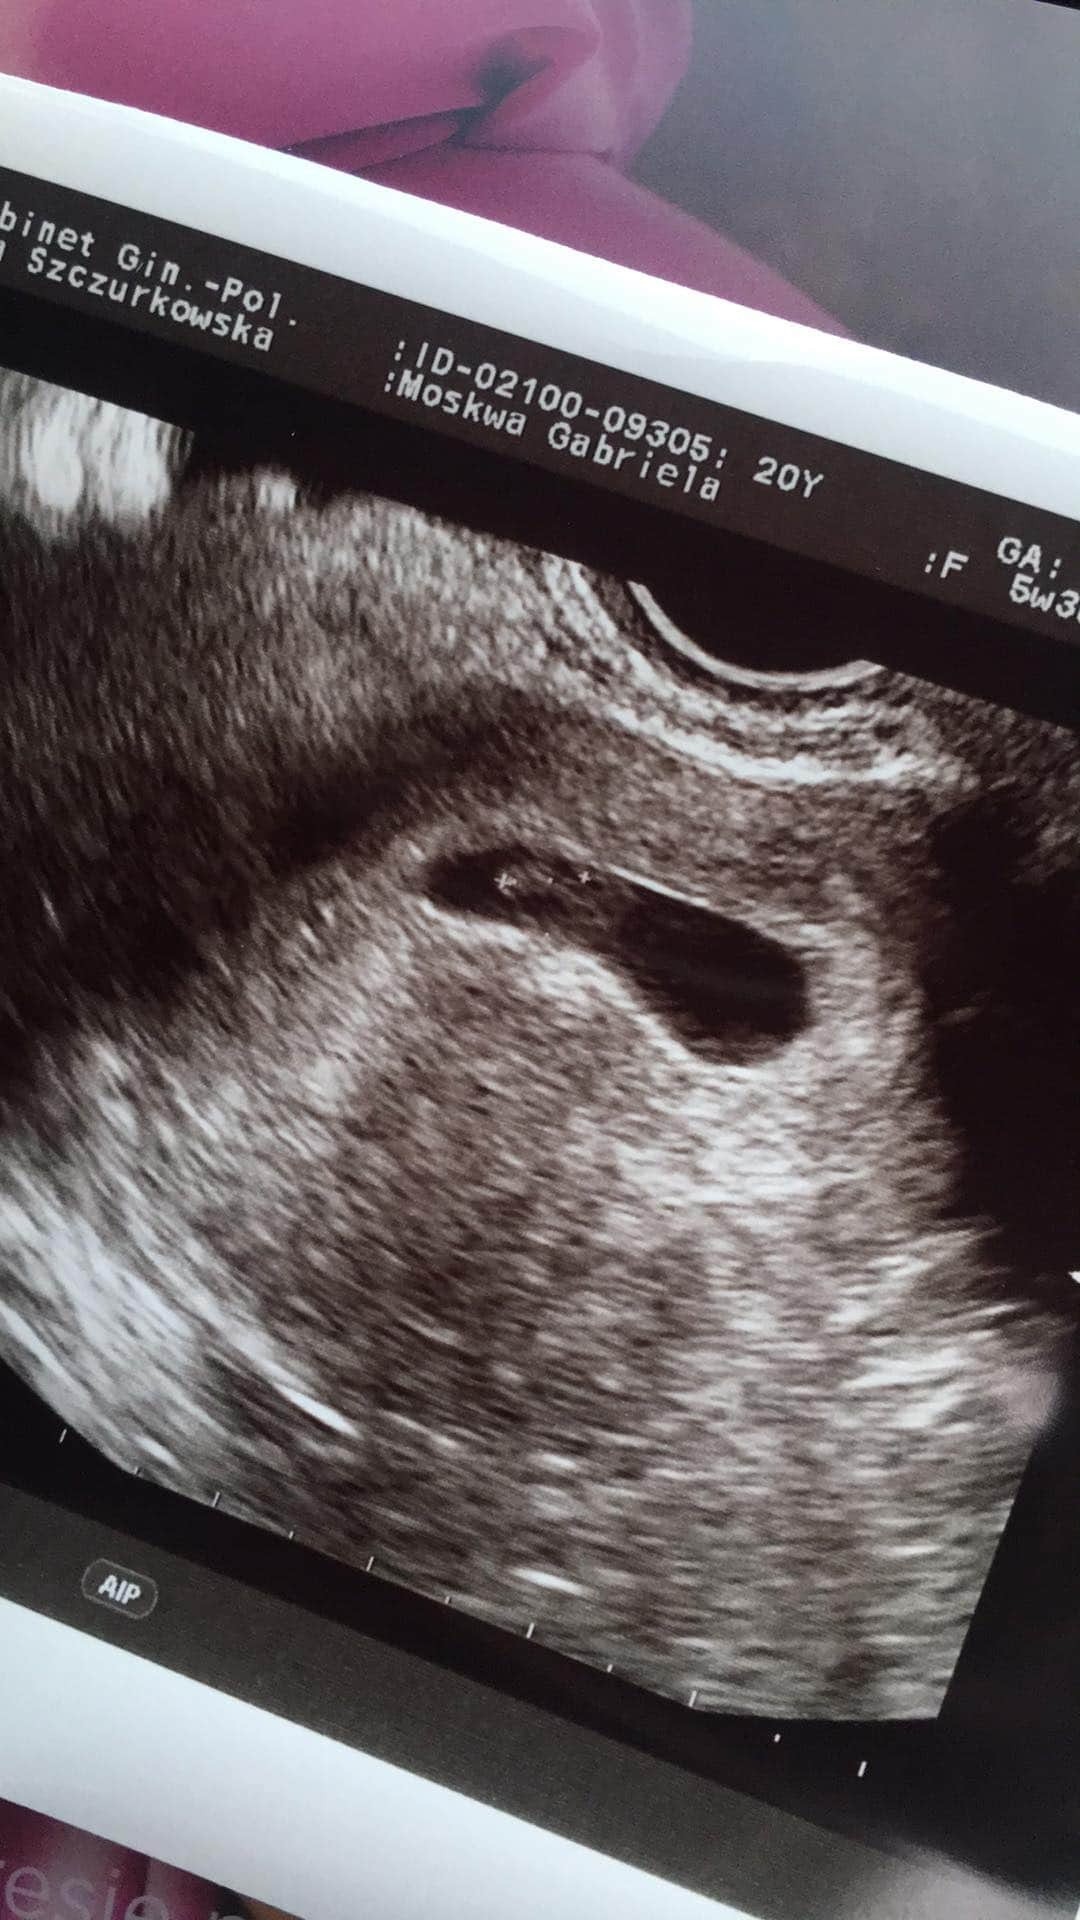

Witam w 6 tyg ciazy licząc od ostatniego okresu :) dzis mialam pierwsza wizyte u ginekologa, widać juz pęcherzyk ciążowy. To moja pierwsza ciaza, mam 32 lata :) niestety mam dwurozna macice, pęcherzyk zagniezdzil sie w jej lewej części. Dostałam dopochwowo progesteron, mamy nadzieje, ze macica się troszkę rozluzni... narazie dolegliwości jako takich brak. Troszkę pobolewa mnie brzuch (rozciąga się macica) i odezwal sie uraz kosci ogonowej sprzed 20 lat. Czy któraś z Was również zmaga się z dwuroznoscia macicy?

Ja się pochwałę zdj z usg :) co widzicie? ❤️